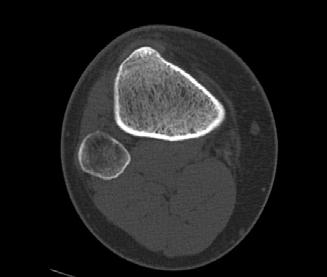

sá sem er mikilvægastur fyrir stöðugleika hnéskeljarinnar. Hnéskelin snertir trissuna fyrst við 20 til 30° beygju um hnéð og við frekari beygju helst hnéskelin stöðug vegna lögunar trissunnar (mynd 1)

Mynd 1

Hliðlægt

Miðlægt